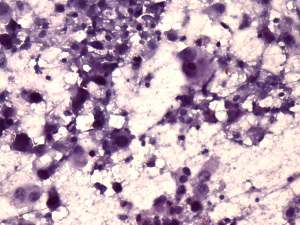

Cytology from the lymph node resulted in metastatic squamous cell carcinoma.

Histopathology disclosed a lymph node metastasis of a basaloid squamous cell carcinoma. The tumor did not spread extracapsular and was HPV-positive. Only one of the 18 removed node contained metastasis.